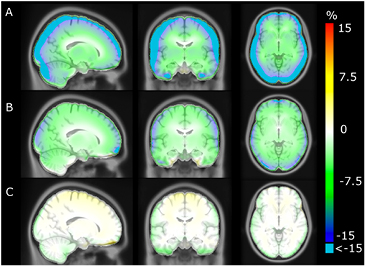

The average error over the full brain was −0.1% (±2.8%), compared to −6.9% (±2.1%) in UTE. The mean absolute error over the full brain was 3.4% (±1.6%), compared to 8.2% (±1.9%) in UTE. The averaged %-difference image from PETCT to PETDIXON, PETUTE and PETRESOLUTE, respectively, is shown in three orientations (figure 6). Notice the error of 10–15% in UTE near the cortex (figure 6(B)). This error is reduced to less than 1% when using RESOLUTE. The results for the averaged joint histograms are shown in figure 7. The values in PETRESOLUTE are closer to PETCT than PETUTE, which is supported by the r2 scores of 0.66 for Dixon, 0.78 for UTE and 0.92 for RESOLUTE. The systematic underestimation compared to PETCT when using Dixon and UTE is significantly reduced when RESOLUTE is applied for MR-AC. A histogram of errors can be seen in supplementary figure 1 (stacks.iop.org/PMB/60/8047/mmedia). We saw an improvement of our method over UTE and Dixon, as the number of voxels greater than ±5% was significantly reduced and the number of voxels around 0% error was increased. The systematic negative bias observed in UTE and DIXON was also considerably reduced.

Figure 6. Averaged %-difference images of 154 patients. (A) shows Dixon, (B) UTE and (C) shows RESOLUTE. Notice that errors of less than −15% are clamped to cyan in A and B.

An image showing the voxel-wise fraction of errors greater than ±5% is presented in figure 8. The probability of having errors greater than ±5% at the cortex is more than 90% when using UTE but only 10–25% when using our method. The probability of an error at the frontal sinus and in the cerebellum is also significantly reduced. Using RESOLUTE, the average fraction of the brain within ±10% and ±5% from PETCT was 95% and 77%, respectively (table 2). In comparison, Dixon/UTE gave 37%/72% within ±10% and 7%/28% within ±5%. The ROI based comparison is presented in figure 9. Using our method, the average error was below −1.2% in all regions of the brain, including the cerebellum, which is often confounded by complex air/tissue interfaces for the regions in the vicinity.

Figure 8. Probability of error greater than ±5% for each voxel. (A) shows Dixon, (B) UTE and (C) shows RESOLUTE.